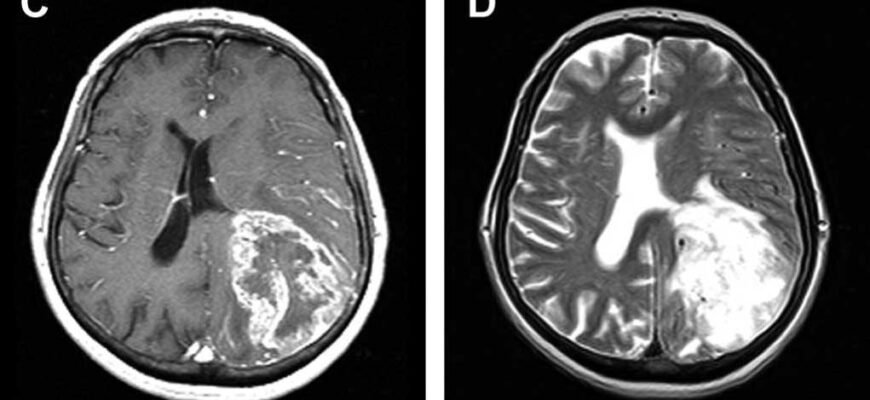

Коли лунають слова «набряк головного мозку», більшість з нас розуміє, що це — серйозно. Але справжні наслідки цієї патології можуть бути настільки багатогранними, що вони часто стають несподіванкою, навіть для досвіду лікарів.

- Інсульти — несподівані звуження та розширення судин. Ось така гра в рулетку.

Кров’яний потік та об’єм: як усе це взаємодіє?

Ну, насамперед, говоримо про те, як важливо підтримувати нормальний кров’яний потік в голові. Це не просто метафора, а справжнє питання життя і смерті. Буквально. І тільки трішки — образно.